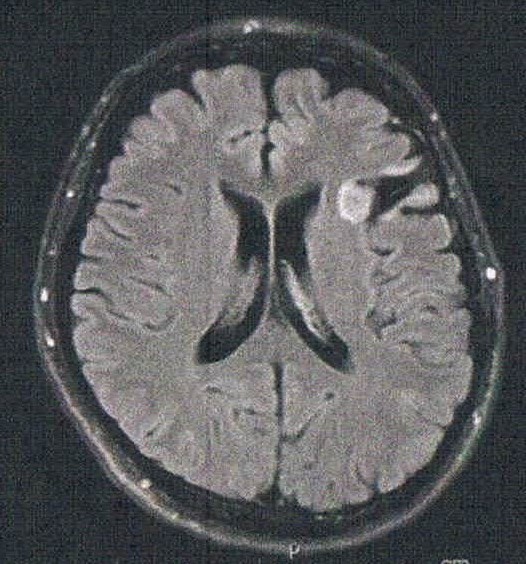

悪性転化しやすい腫瘍の種類(びまん性星細胞腫グレード2)であるとのことで造影剤を注射してMRI検査をする。4時間前から絶食し、MRIの1時間前に血液検査を済ませる。コロナで緊急事態宣言下であるからか院内は空いていて待ち時間は短い感じ。

診断の結果は特に変化はなく問題なし。造影剤がしみ込んでいる箇所もないとのことで、悪性度は低い状態を保っているとのこと。良かった!